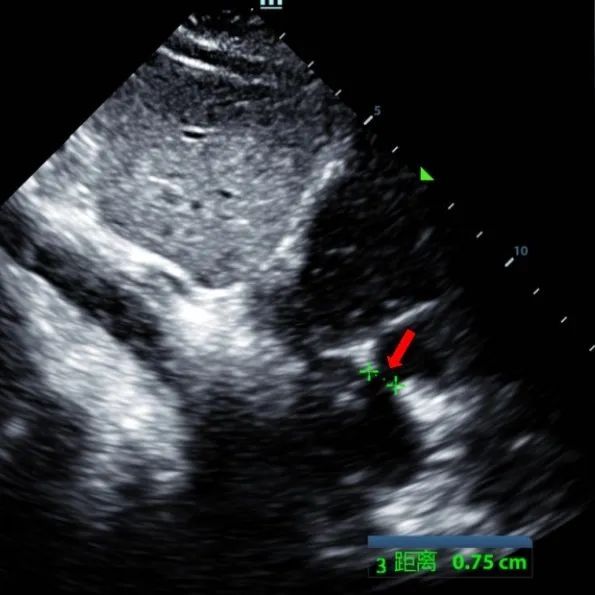

Secundum ASD (7.5〜7.9mm) の9歳の男性は、MemoSorb BDASD-I 12 mmオクルーダーおよび12Fデリバリーシステムを使用して治療されました。 手順前に合併症や併存症は見られませんでした。

Serial echocardiographic follow-ups showed stable device position and favorable cardiac remodeling. Gradual degradation confirmed the occluder's long-term safety and efficacy.